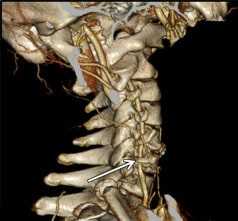

![Аномалия Киммерли]()

Аномалия Киммерли

Патологическая костная дужка на 1 шейном позвонке. Позвоночная артерия проходит через узкое костное отверстие перед входом в череп. В ряде случаев её компрессия может вызывать синдром позвоночной артерии с мучительными жалобами. На фотографии показана эта аномалия, выявленная при обследовании.

- Сдавление артерии при аномалии Киммерли